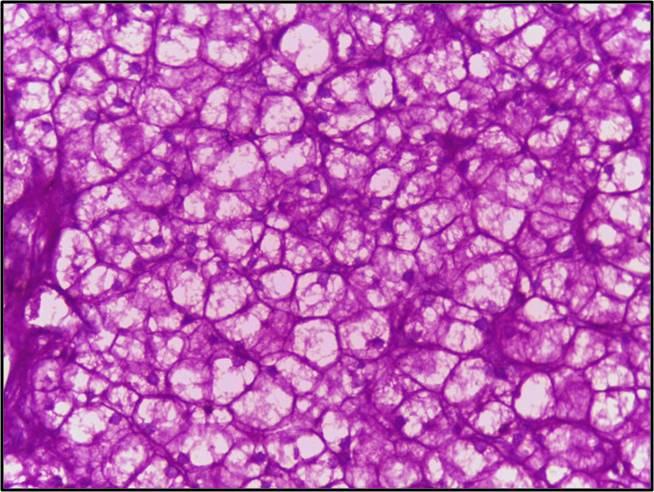

The periodic acid of the stain reacts with carbohydrates in an oxidative process. In this process, the polysaccharide and the periodic acid reaction form an oxidized compound- aldehyde. Now, the aldehyde reacts with the Schiff reagent, which gives the purple-magenta color. Similarly, the appearance of the pink color suggests the presence of intracellular or extracellular mucin. In contrast, using hematoxylin or methyl green as counter-stain helps in staining the nuclei. Likewise, a light green colored counter stain is preferred to demonstrate the fungal organisms.

Results interpretation for Periodic acid-Schiff (PAS) Staining

- Glycogen, mucin and some basement membranes-Red/ purple

- Fungi-Red/ purple

- Background-Blue